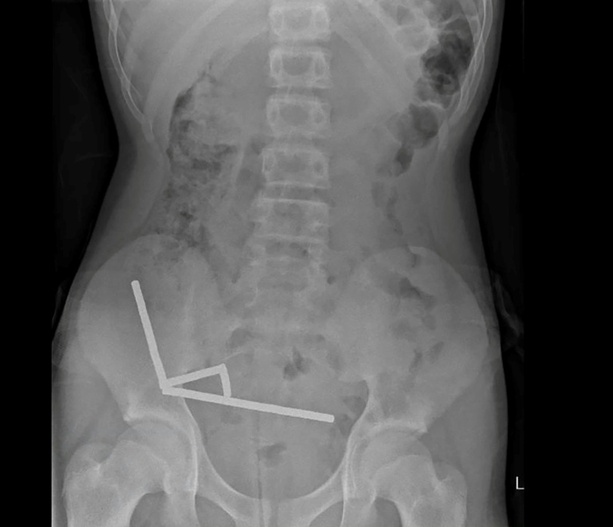

Die Magneten, die in Neuseeland seit Anfang 2013 verboten seien, seien auf der Temu-Plattform gekauft worden, teilten die Ärzte mit. Eine Röntgenaufnahme habe gezeigt, dass die Magneten sich in verschiedenen Bereichen des Darms aufgrund der Anziehungskraft zu vier geraden Linien zusammenklumpten. Den Ärzten zufolge starb durch die Kraft der Magneten an vier Stellen im Dünn- und Dickdarm Gewebe ab.Â